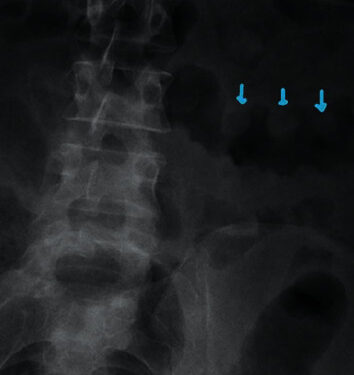

Пациенту был назначен ряд начальных лабораторных и визуализирующих исследований, а также последующая диагностика на основе этих результатов (таблицы (Таблицы11 и и 2). Рентген брюшной полости (Рисунок 1) продемонстрировал классический признак отпечатка большого пальца, который был неспецифическим, но подозрительным на инфекцию Clostridium difficile. Эмпирические антибиотики внутривенно метронидазол и пероральный ванкомицин были начаты для предполагаемой инфекции Clostridium difficile в ожидании лабораторных тестов и результатов гистологии.